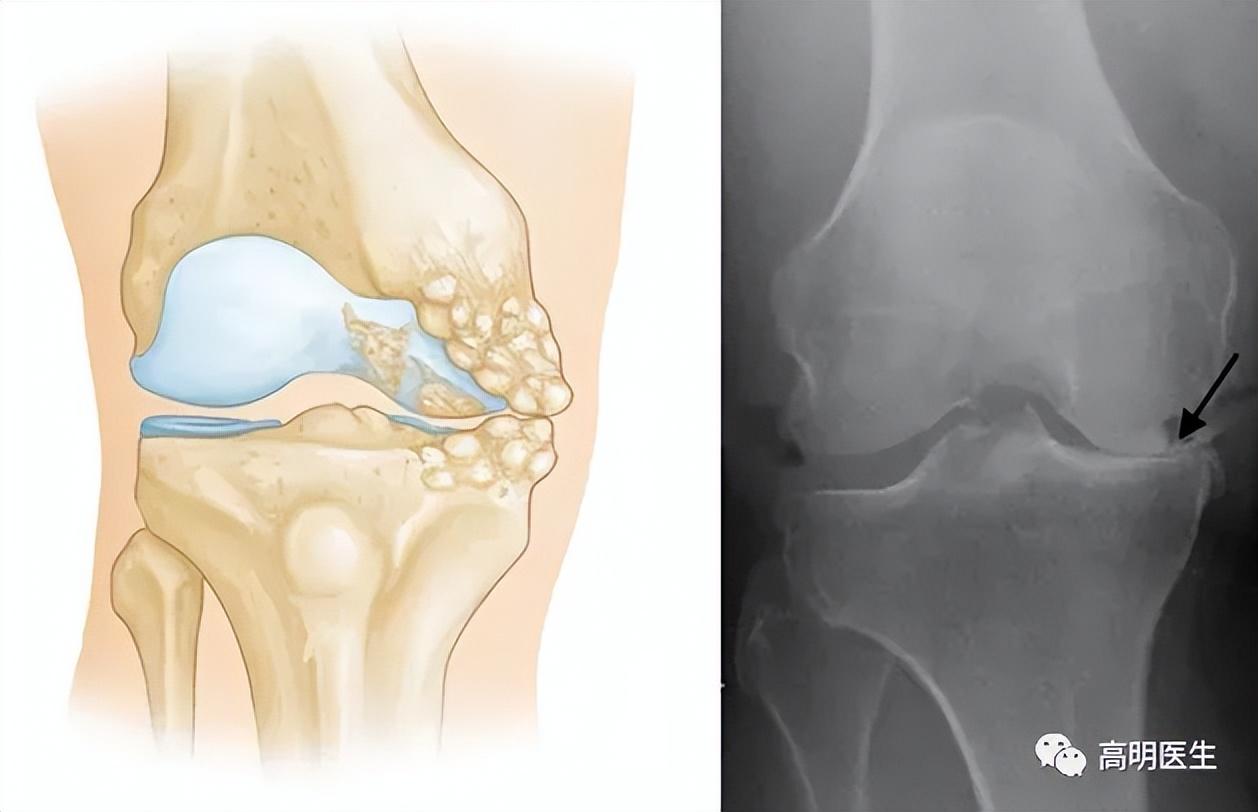

膝關節骨性關節炎,是一種膝關節的退行性疾病,主要臨牀表現爲膝關節疼痛、腫脹及活動受限,主要病理表現爲膝關節軟骨的纖維化、磨損、剝脫等伴發滑膜充血水腫及骨贅增生等。

· 骨關節炎:最常見的類型,主要由關節軟骨的退化引起。年齡增長、肥胖、過度使用關節、遺傳因素等纔是主要發病原因。

關節就像汽車輪胎,也有“使用壽命”。隨着年齡增長,關節軟骨逐漸磨損,彈性下降,最終出現骨贅(俗稱“骨刺”),這就是骨關節炎的過程 。 只不過有些人的關節耐磨,有些人的不耐磨罷了。